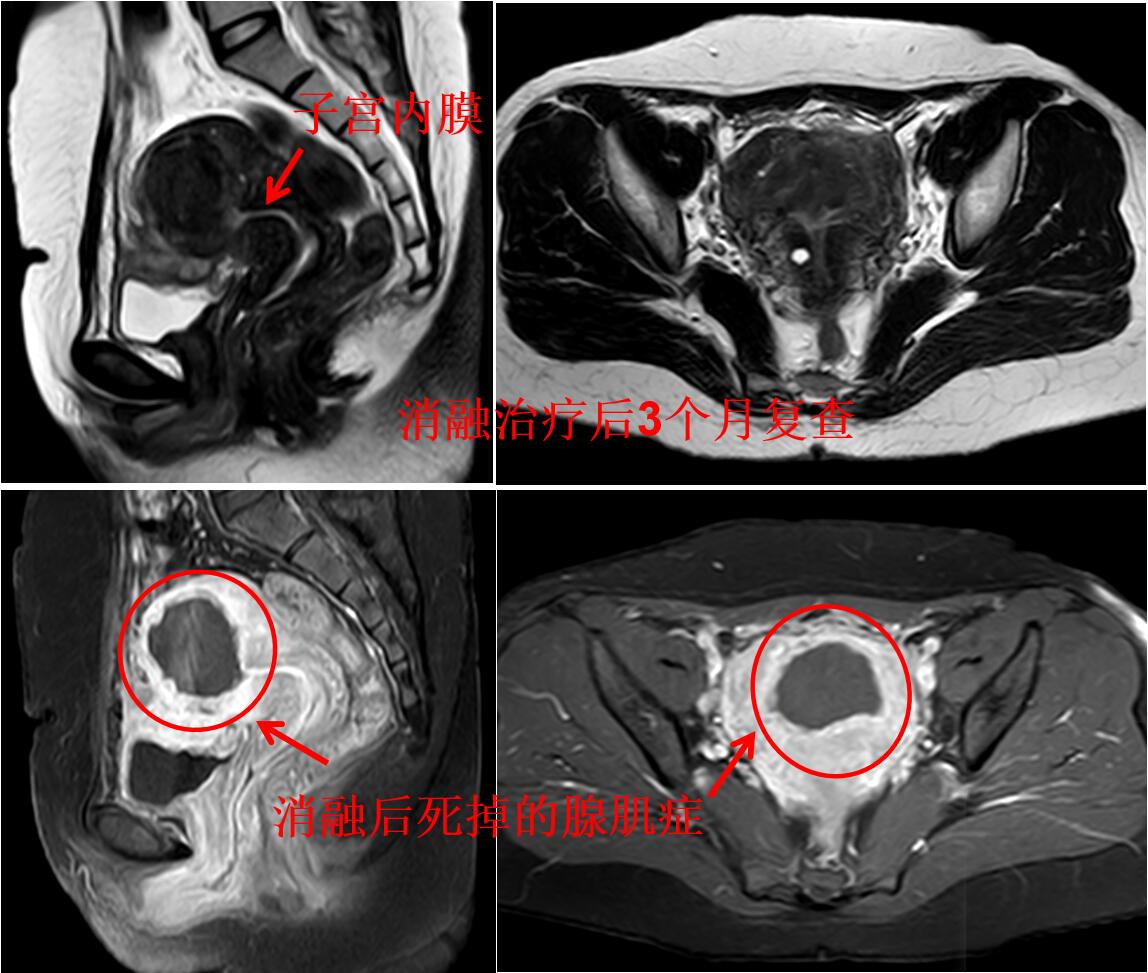

门诊磁共振检查:子宫明显增大(10.8*9.2*8.7cm3),子宫腺肌症,以宫底及后壁明显(如下图)。

介入微创消融治疗后无明显痛经,3个月后复查磁共振显示:子宫腺肌病病灶灭亡,子宫缩小(如下图)。

介入微创消融治疗后1年痛经没法复发,复查磁共振显示:子宫大小恢复正常,腺肌症灭亡吸收排出(如下图)。